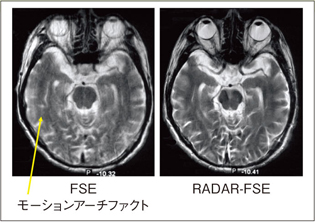

RADARによるモーションアーチファクト低減画像例を図8〜11に示します。

図8はSE法による頭部T1強調画像で,血流のアーチファクトがRADAR-SEの適用により低減されています。図9はパーキンソン病症例で,頭部のモーションアーチファクトが低減されています。図10は卵巣嚢腫症例で,腹壁の呼吸によるアーチファクトの顕著な低減効果が得られています。同様に,図11は子宮筋腫症例で,アーチファクトが低減されています。

![]() 図9 パーキンソン病T2強調画像 |